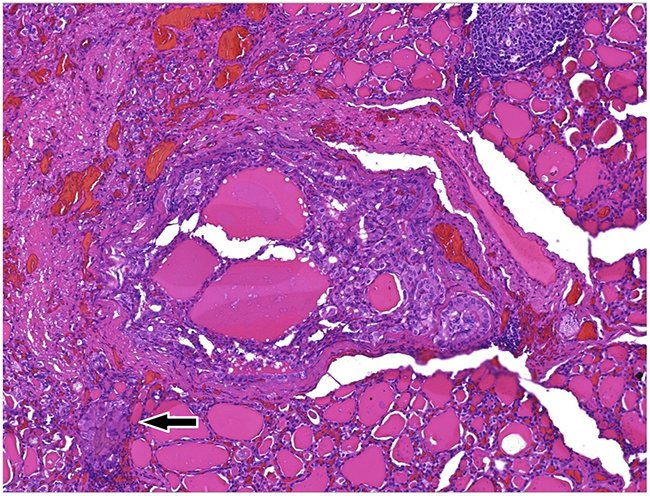

Histological examination of the lesion showed a proliferation of well differentiated epithelial cells forming an purely papillary structure surrounded by blood vessels, with irregular borders, overtly infiltranting thyroid parenchyma.

The neoplasm showed no relationship to thyroid capsule and no vascular or lymphatic invasion. All the lymph nodes retrieved were devoid of metastatic cells (final TNM 8th eds. staging pT1, pN0) (Figure 11).

Figure 11: (100x) Whole section of the PTMC, classic variant, Ø 0.3 cm, devoid of a capsule structure, being made offollicoles and well formed papillae with fibrovascular core, irregular contour, surrounded by newly formed microvessels. White arrow highliths a papillary group of neoplastic cells penetrating normal thyroid follicoles at the periphery of the main focus, which indicates that the tumor already shows tendency to spread in the surrounding (invasion).

Cut surfaces showed a whitish equatorial nodule of 0.3x0.2x0.2 cm in the left lobe.

On histological examination the lesion was classified as papillary thyroid microcarcinoma (PTMC, classic variant), the neoplasm beeing made of well formed papillae intermingled focally with normal thyroid parenchima. Lymph node showed no involvement by tumor cells, and pathological stage was pT1a, pN0 according to TNM 8th edn [33, 34, 35].